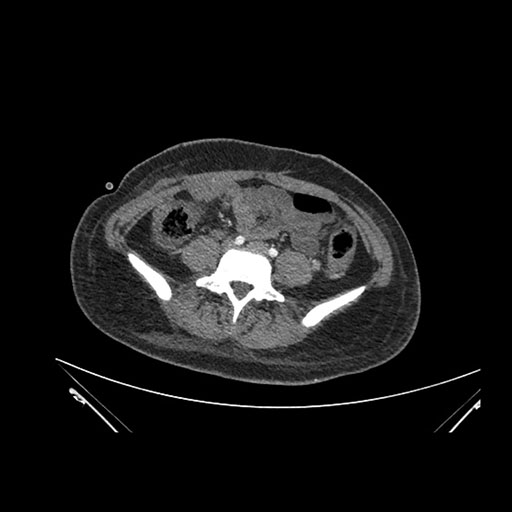

Vasculobiliary injury [M28]

Imaging Analysis

Look through the patient's CT scan to identify any areas of concern for the necessary procedure.

Axial Arterial

Axial Venous